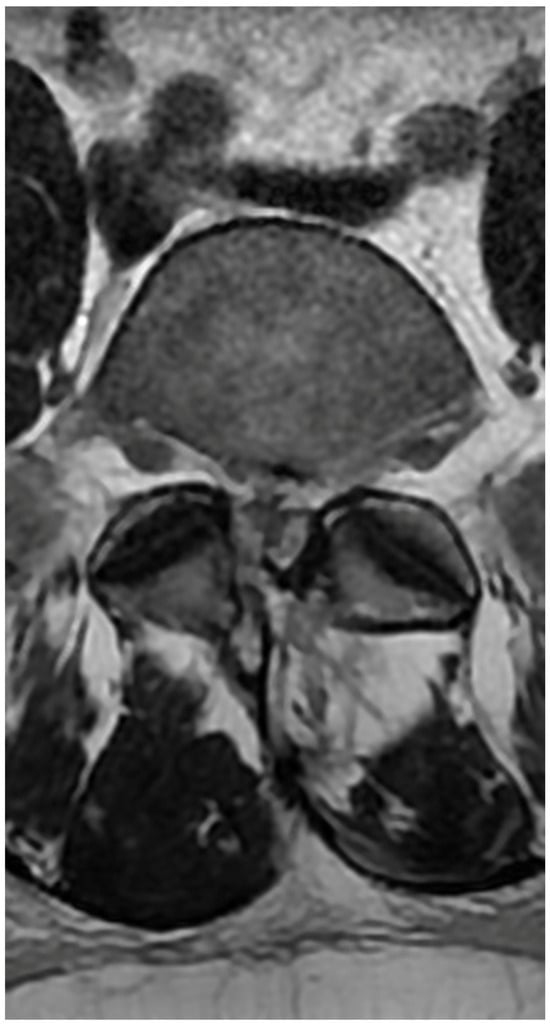

3.4. Case 1: Transient Cauda Equina Syndrome Due to Subdural Hematoma

- Case 1: Incidents of postoperative cauda equina syndrome are documented in the context of traditional surgical approaches. In our literature review, we identified a singular case of postoperative cauda equina syndrome, which, however, pertained to a patient following endoscopic intervertebral stabilization. This incident was associated with the migration of bone material into the dural sac [43]. Our case suggests that previous surgery, leading to scarring and adhesions, and anatomical challenges such as steep and large facet joints, might have contributed to the complication by complicating root mobilization and endoscope trajectory.